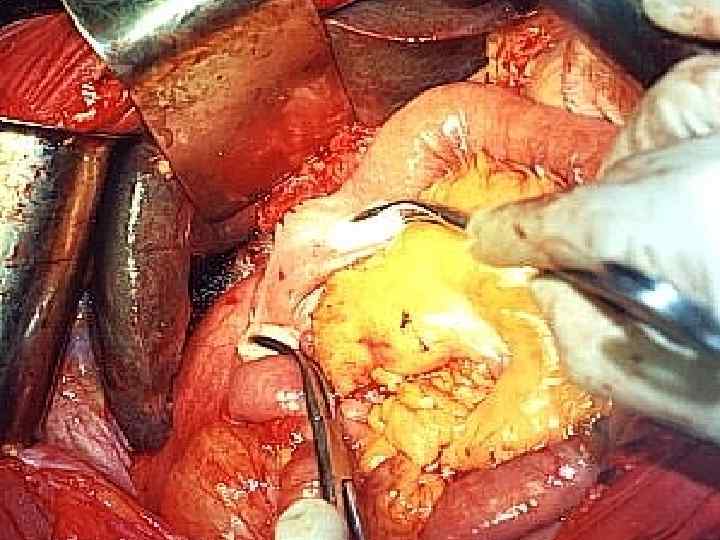

Распространенность протокового рака головки ПЖ в момент «радикальной» операции 1. 2. 3. 4. 5. 6. 7. Инвазия передней капсулы ПЖ – 80% Инвазия края резекции ПЖ – 40% Ретроперитонеальная внеорганная инвазия – 80% Инвазия крупных сосудов – 60% Метастазы в регионарные лимфоузлы – 100% Метастазы в юкстарегионарные лимфоузлы – 80% Метастазы в печень – 20%